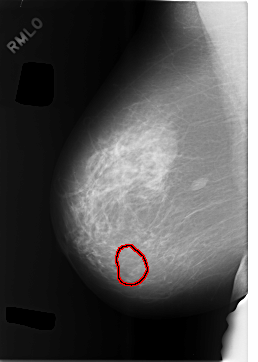

C_0479_1.RIGHT_MLO

RIGHT_MLO LINES 5792 PIXELS_PER_LINE 4120 BITS_PER_PIXEL 12 RESOLUTION 50 OVERLAY

FILE: C_0479_1.RIGHT_MLO.OVERLAY

TOTAL_ABNORMALITIES 1

ABNORMALITY 1

LESION_TYPE MASS SHAPE OVAL MARGINS CIRCUMSCRIBED

ASSESSMENT 3

SUBTLETY 5

PATHOLOGY BENIGN

TOTAL_OUTLINES 1

BOUNDARY